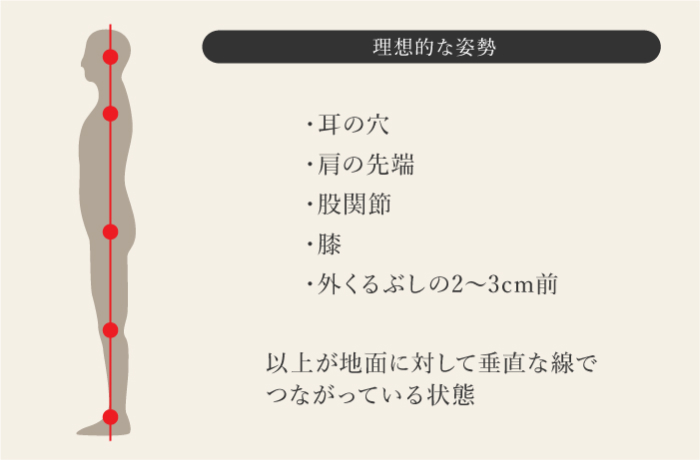

- 姿勢指導